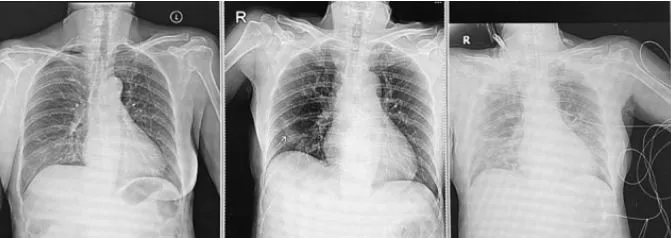

เอกซเรย์ปอดยังปกติ อีกวันถัดมาอาการปอดอักเสบชัดขึ้น คนไข้หายใจเหนื่อยจนระบบหายใจล้มเหลวอย่างรวดเร็วและใส่ท่อช่วยหายใจ ย้ายเข้าห้องไอซียู คนไข้อาการหนักมาก เข้าใจความรู้สึกของลูกที่รู้ทีหลังว่าแม่ตัวเองต้องมานอนไอซียูเพราะไม่ระวังเรื่องการกักตัว